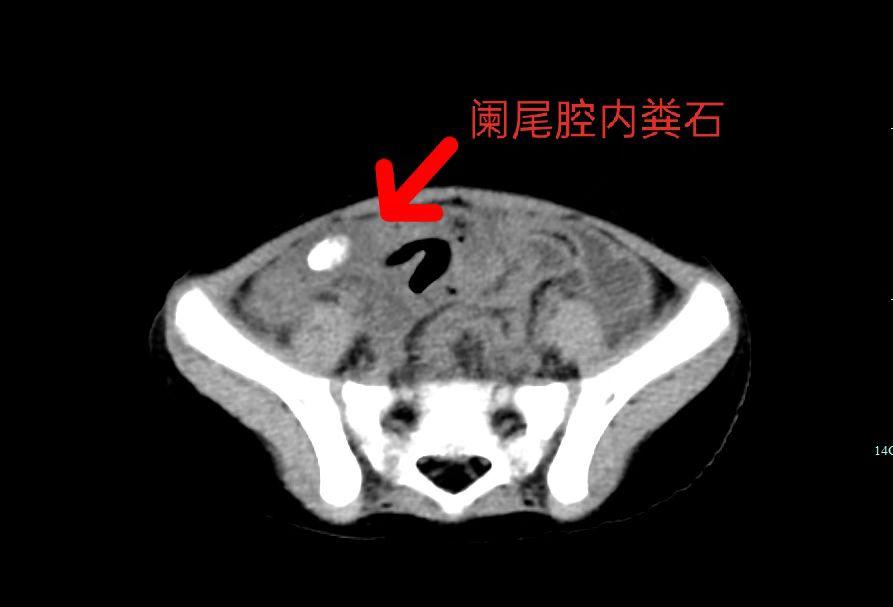

在亚星手机版官方登录内镜中心,有间诊疗室一改其他诊室的安静氛围,孩子哭喊声陆续传来。这里是小儿支气管镜诊疗室。时间来到2022年8月12日,4岁的小项因持续发热、咳嗽长达5天,......